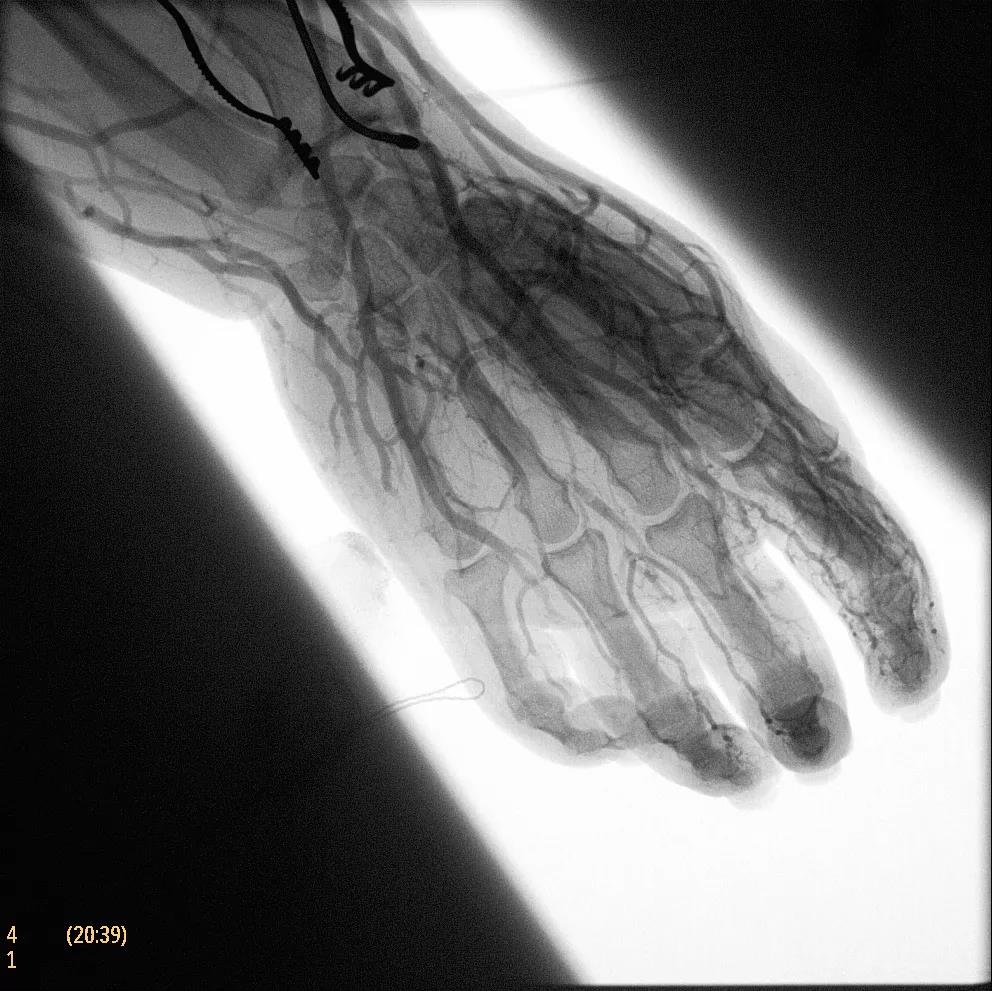

為了獲得清晰的高質(zhì)量圖像,Zenition 70 采用了與公司Azurion平臺(tái)相同的圖像處理算法,可提供患者解剖結(jié)構(gòu)的高清可視化和更大的可視區(qū)域。飛利浦的MetalSmart軟件等功能可確保圖像質(zhì)量,該軟件可自動(dòng)調(diào)整圖像的對(duì)比度和亮度,以便在視野中存在金屬物體(如植入物)時(shí)提高圖像質(zhì)量 - 這一特性使Zenition 70在整形外科中特別有用。